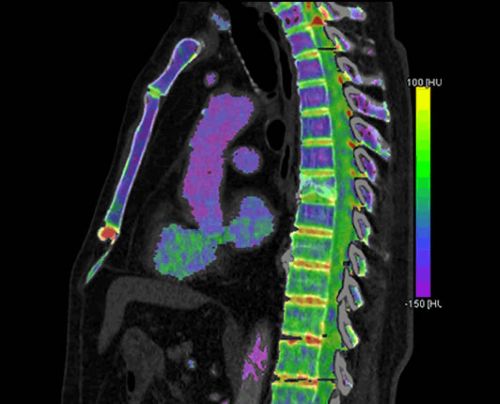

ხერხემლის სვეტის კომპიუტერული ტომოგრაფიის შედეგების ანალიზის დროს დიდი მნიშვნელობა აქვს მულტიპლანურ რეკონსტრუქციას, რომლის მეშვეობითაც შეიძლება ინტერპრეტაცია მიეცეს არა მარტო მიღებულ აქსიალურ, არამედ საგიტალურ, ფრონტალურ და ირიბ ჭრილებს.

ხერხემლის სვეტის კომპიუტერულ-ტომოგრაფიული გამოკვლევისას ჩვეულებრივ ვიყენებთ ტომოგრაფიულ ჭრილს ყოველ 3 მმ-ში. ხერხემლის ერთი სეგმენტის შეასაწავლად საკმარისია 8-12 კომპიუტერული ტომოგრამა. თითოეული შემთხევივისათვის აუცილებლად ტარდება მულტიპლანური რეკონსტრუქცია საგიტალურ და ფრონტალურ სიბრტყეებში, ხოლო საჭიროების შემთხვევაში - ირიბ ჭღილებშიც. რეკონსტრუქციის ხაზი გადის დისკის თიაქარის აქსიალურ პროექციაში მაქსიმალურად გამოსულ ნაწილზე.

მალთაშუა დისკის დენსიომეტიული მაჩვენებლები 75-100 ერთეულ Н-ს უდრის. წყლის დაბალი შემცველობისა და ცილების მაღალი კონცენტრაციის გამო სხეულის შეადგენს ღრუბლისებური ნივთიერების სიმკვრივე 170±55 ერთეულს. ათეროსკლეროზის დროს სიმკვრივე შეიძლება გაიზარდოს 500 ერთეულ Н-მდე, ხოლო ოსტეოპოროზის დროს შემცირდეს 0 ერთეულ Н-მდე. ყველაზე ხშირად დისკის დეფორმაცია ფიქსირდება ხერხემლის L4–L5, L5–S1 სეგმენტებში.